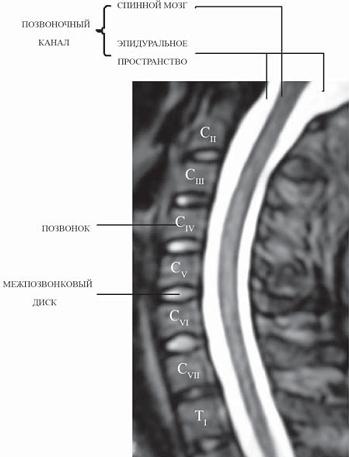

МРТ № 1

На магнитно-резонансной томографии (МРТ) № 1 — шейный отдел позвоночника, в относительно нормальном состоянии.

Шейный отдел позвоночника должен иметь нормально выраженный физиологический лордоз, не должно быть гиполордоза или гиперлордоза, а так же кифотических деформаций.

Ширина спинного мозга: сагиттально > 6–7 мм

1. Сагиттальный размер позвоночного канала на уровне:

СI ≥ 21 мм

СII ≥ 20 мм

СIII ≥ 17 мм

CIV-CVII = 14 мм

2. Высота межпозвонковых пространств:

СII < СIII < СIV < СV < СVII ≥ СVII

3. Ширина спинномозгового канала: поперечный диаметр на уровне ножек: > 20–21 мм